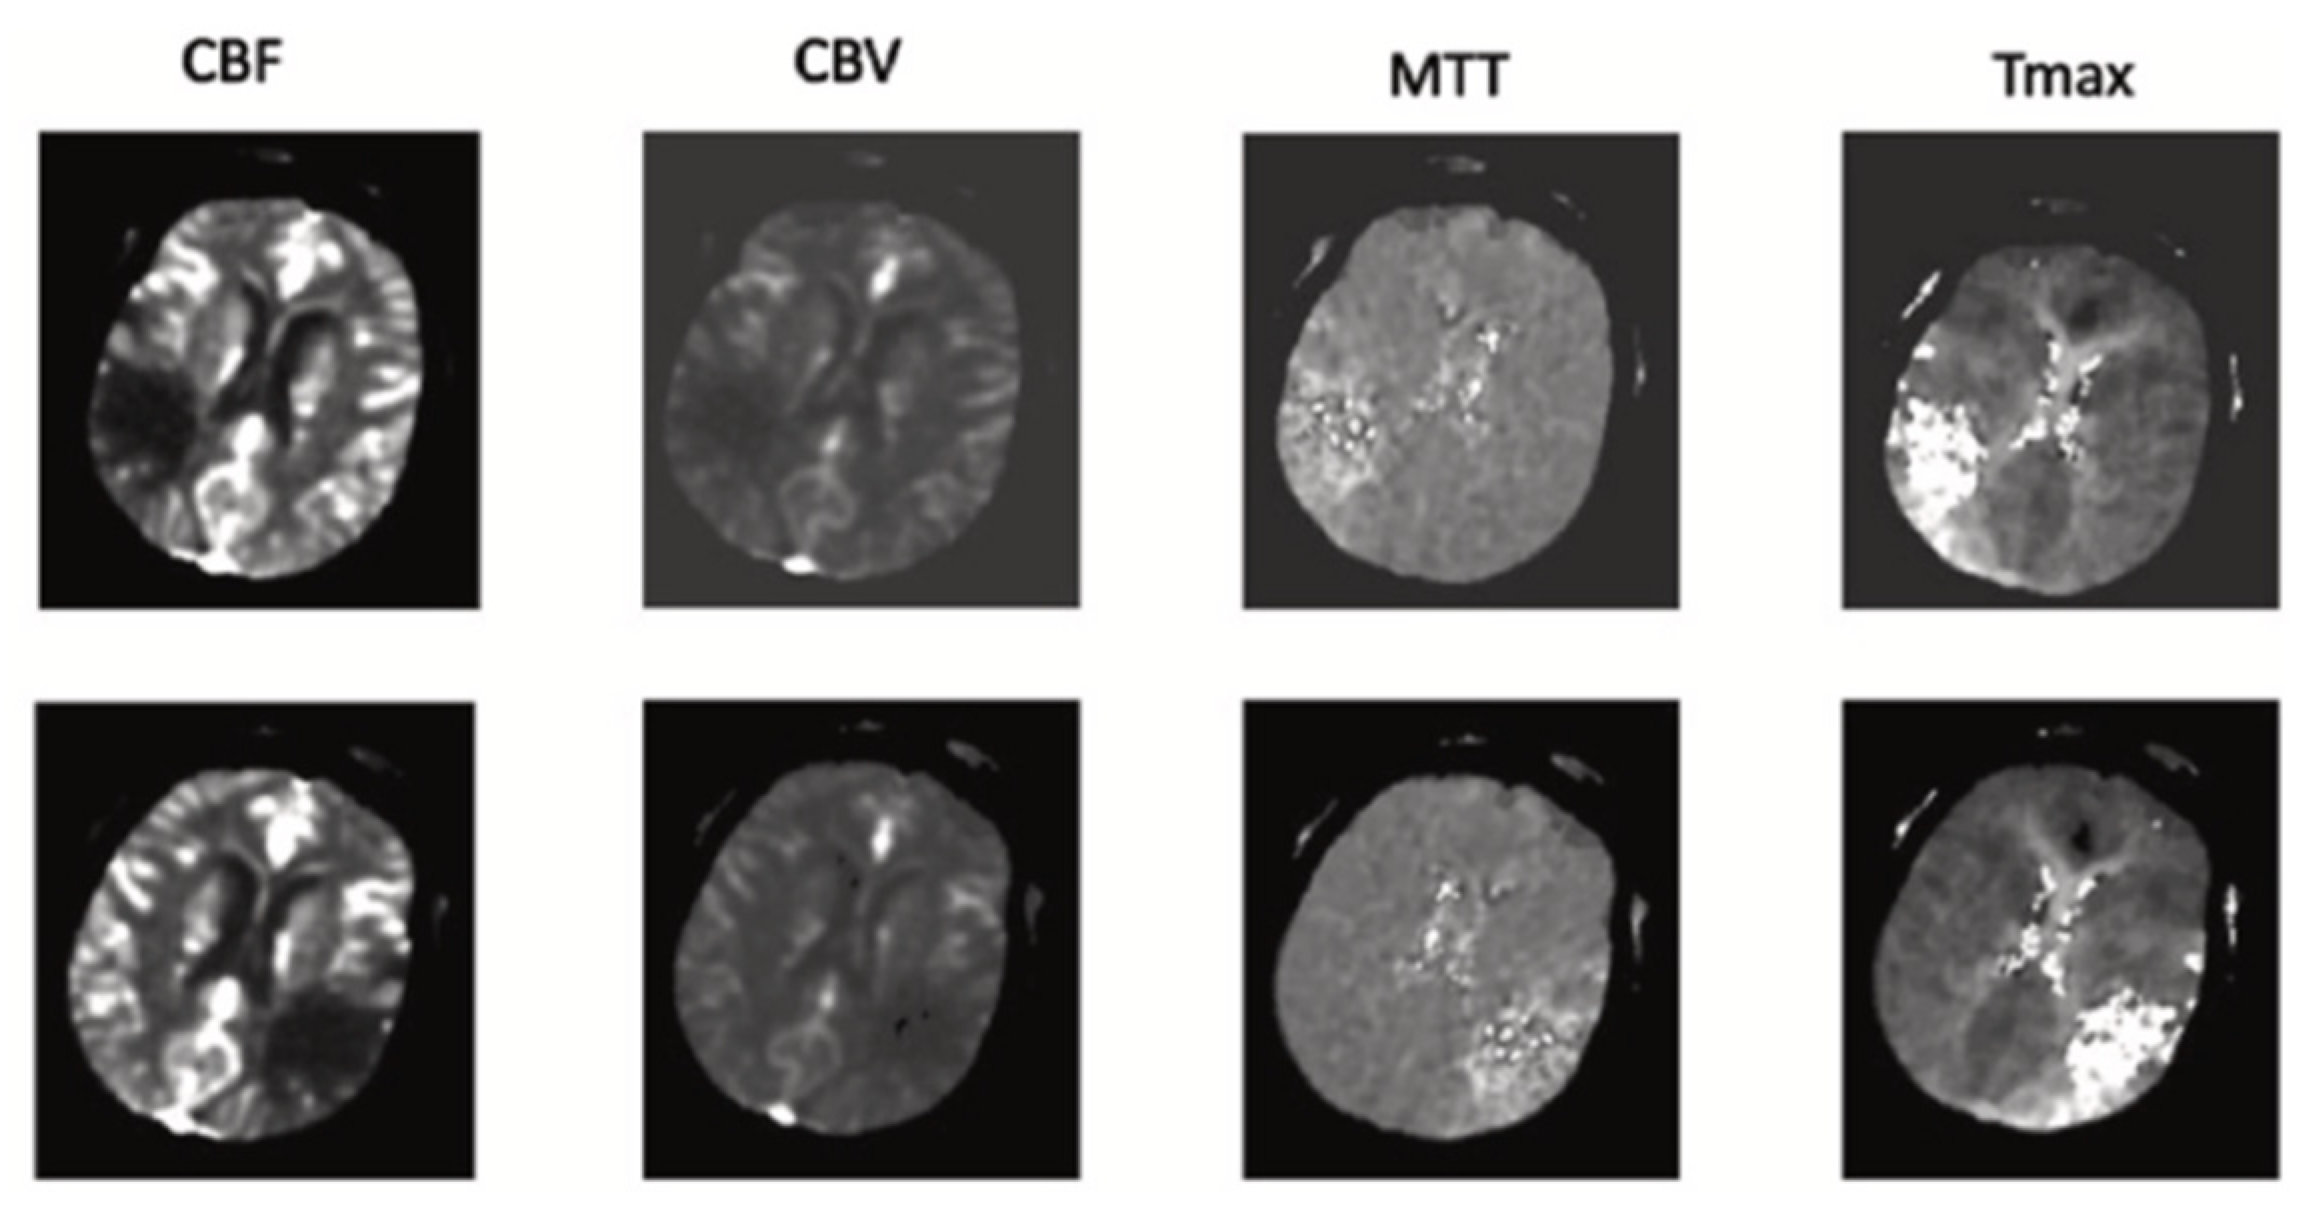

- The proposed network utilizes a channel of perfusion maps, including CBV, CBF, MTT, Tmax, and CT slice, to efficiently extract the stroke lesion.

| CT Stroke Lesion | Category | Total Images | Dimension | Number of Train Images | Number of Test Images |

|---|---|---|---|---|---|

| 1 | CBV | 502 | 256*256 | 450 | 52 |

| 2 | CBF | 502 | 256*256 | 450 | 52 |

| 3 | MTT | 502 | 256*256 | 450 | 52 |

| 4 | Tmax | 502 | 256*256 | 450 | 52 |

| 5 | CT | 502 | 256*256 | 450 | 52 |